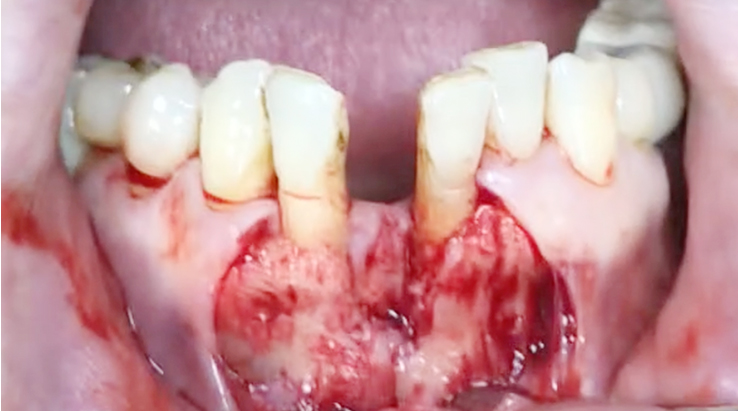

Implants/Bone Grafting

Simultaneous bone graft and implant placement